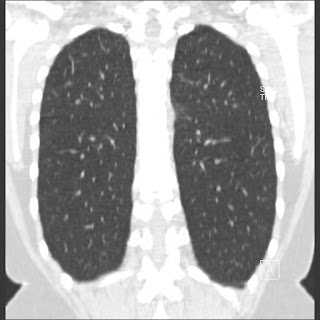

New CT images (without contrast) for 40 year old female with silicone breast implants. Formal diagnosis is expected soon. Images from 2010 can be seen here http://radiology-images.blogspot.com/p/40-year-old-female-silicone-implants.html

Please see also already added images in sagittal view Sagittal